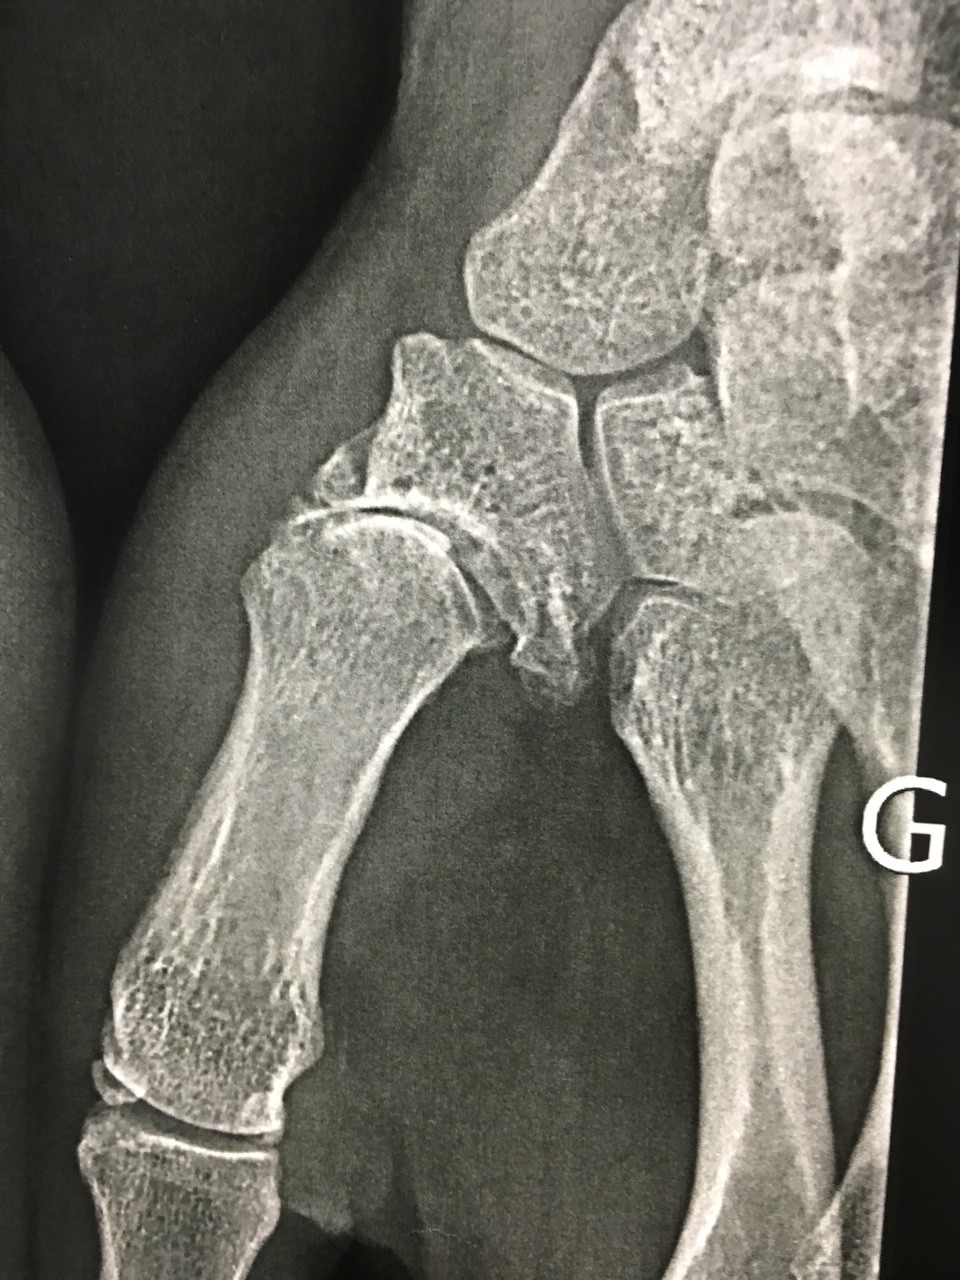

Le diagnostic se fait dès l’examen clinique. Les radiographies de l’articulation trapèzo-metacarpienne selon les incidences de Kapandji peuvent suffire dans la majorité des cas. Dans certains cas complexes, un scanner sera prescrit par le chirurgien. Un syndrome du canal carpien touche pratiquement un tiers des femmes concernées par l’arthrose de la base du pouce. Il est alors possible d’envisager le traitement des deux problèmes en même temps. Il est donc justifié de réaliser un électromyogramme dans le cadre du bilan avant traitement.

Le traitement est médical dans un premier temps. Des anti-inflammatoires sont prescrits en cas de poussée pour une courte durée. Je recommande également et en même temps le port d’une petite orthèse que l’on trouve en pharmacie. Celle-ci peut être portée la nuit pour mettre le pouce au repos. C’est relativement efficace au début. Des infiltrations peuvent s’avérer utiles mais elles ne permettent pas de stopper l’évolution, ni traiter la cause. Si le traitement médical ne permet plus un soulagement durable, la chirurgie doit être envisagée et il n’est pas toujours très prudent d’attendre que les déformations soient graves. Moins le pouce est déformé plus le résultat fonctionnel est bon. Il existe trois grandes façons de traiter l’arthrose de la base du pouce :

-Le remplacement par une prothèse (arthroplastie)

-l’ablation de l’os malade (trapezectomie)

-le blocage de l’articulation (arthrodèse totale)

Chaque opération a ses avantages et ses inconvénients, chaque cas est particulier. L’opération dont il est le plus facile de se remettre est l’implantation d’une prothèse totale qui permet de retrouver une bonne fonction mais elle n’est pas possible en cas de déformation très importante. Le choix de l’opération se fait avec le chirurgien en fonction de vos habitudes de vie, de votre demande fonctionnelle et en fonction de paramètres médicaux.